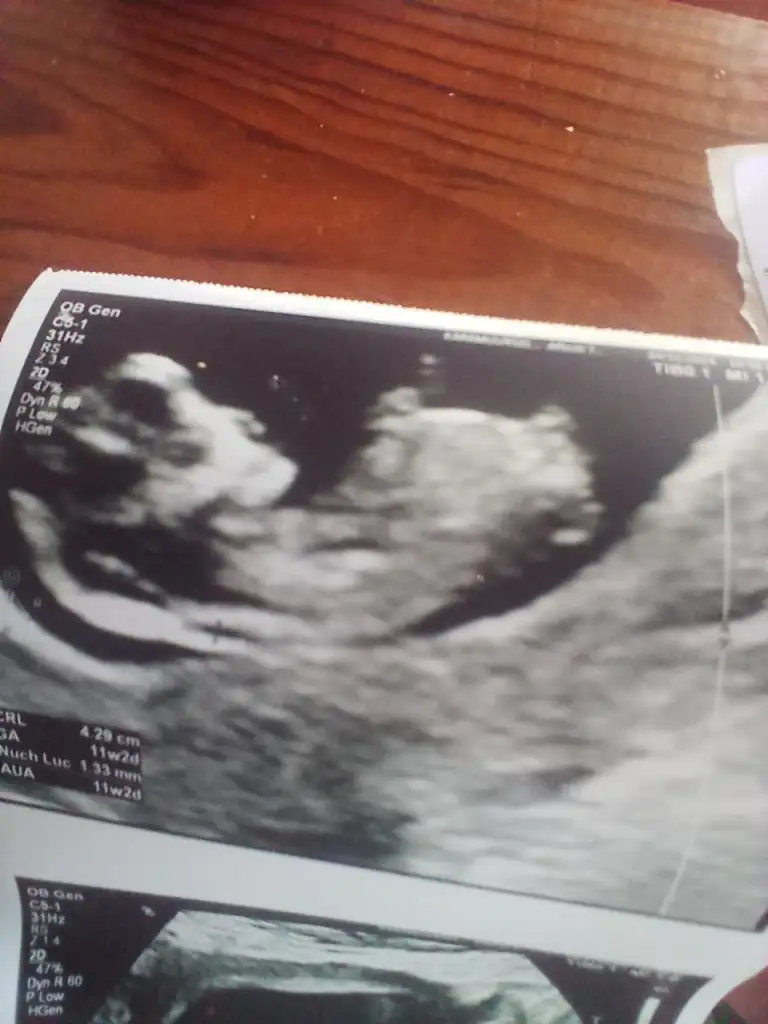

Bizde yorum alabilirmiyiz

Merhaba evet benziyor gibi ama ben pek anlamıyorum kaç haftaliksiniz bende dr söyleyince öğrendim gönlünüzden gecenin nasip olmasını dilerim

12 haftalık. Doktor bir tahminde bulundu. Kız gibi ama üstten bacak arasına da bakayım dedi üstten bir türlü göremedi. Alt popo tarafından açtı ayağını arası boş dedi. Ama daha küçük 1-2 haftaya netleşir dedi.